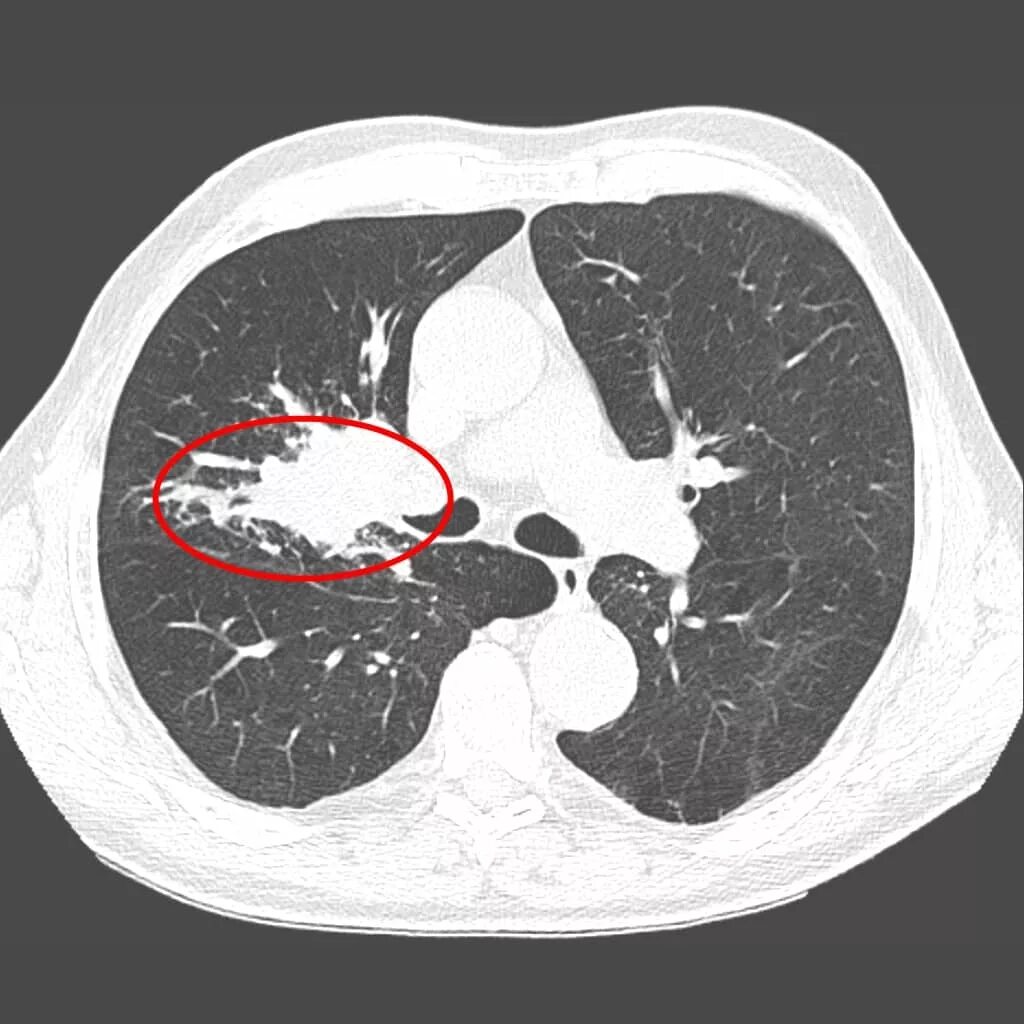

Как на кт выглядит рак